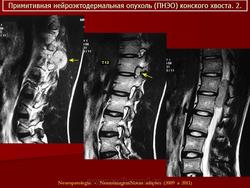

Примитивная нейроэктодермальная опухоль (pPNET)

Периферическая примитивная нейроэктодермальная опухоль (pPNET)